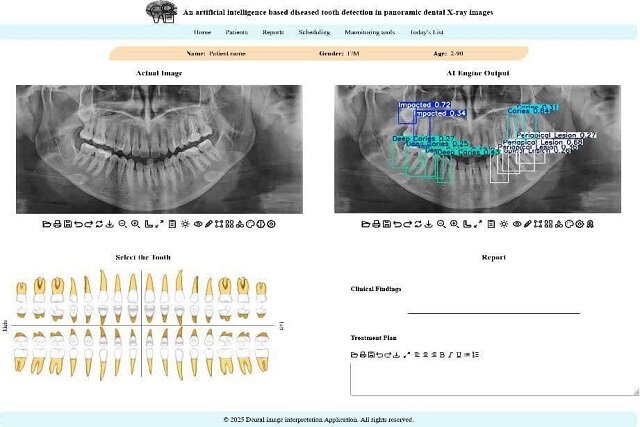

استاد دانشکده مهندسی برق و کامپیوتر دانشگاه تهران با بیان اینکه در این پژوهش جدید محققان تلاش کردهاند تا این چالش را با کمک فناوری حل کنند، افزود: برای این منظور یک سامانه تشخیصی مبتنی بر هوش مصنوعی طراحی شده است که این سامانه، معماری پیشرفته شبکه عصبی به نام YOLOv11 است که آموزش آن بر روی یک مجموعهداده عمومی انجام شده است. این مدل قادر است بهصورت خودکار، محل دقیق ضایعات و ناهنجاریها را در تصویر شناسایی کرده و احتمال درستی تشخیص خود را نیز اعلام کند.

ظروفی یکی از نقاط قوت این پژوهش را کاربردی شدن پژوهش در قالب یک اپلیکیشن وب، عنوان کرد و گفت: یکی از نقاط قوت این پژوهش، کاربردی بودن آن است. این مدل در قالب یک اپلیکیشن تحت وب پیادهسازی شده تا دندانپزشکان و رادیولوژیستها بتوانند به سادگی از آن استفاده کنند. این سامانه با مشخص کردن محل دقیق مشکلات، به پزشک در اولویتبندی و تصمیمگیری سریعتر کمک میکند.

وی همچنین افزایش سرعت و اطمینان در تصمیمگیری بالینی را از دیگر مزیتهای استفاده از این سامانه در تشخیص مشکلات دندانپزشکی برشمرد و افزود: به گفته کارشناسان، بهرهگیری از چنین سامانههایی نه تنها سرعت فرآیند گزارشنویسی را افزایش میدهد، بلکه به عنوان یک ناظر دوم، میتواند با کاهش خطاهای ناشی از خستگی یا حجم بالای کار، دقت تشخیص نهایی را ارتقا دهد و نقش مکملی مؤثر برای متخصصان فک و صورت ایفا کند.

بر اساس نتایج این تحقیق، مدل پیشنهادی در مقایسه با نسخههای قبلی، دقت بالاتری در شناسایی و طبقهبندی ناهنجاریها از خود نشان داده است.